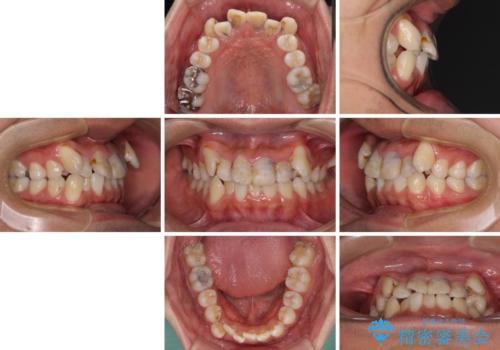

- 八重歯と上顎前歯の変色を気にして来院された患者様です。

上下ともに八重歯が顕著であったため、上下左右の第一小臼歯4本を抜歯し、ワイヤー装置での抜歯矯正を行うこととしました。

前歯は根管治療が必要な歯を事前に根管治療を行い、矯正治療後にオールセラミッククラウンにて補綴治療を行うこととしました。